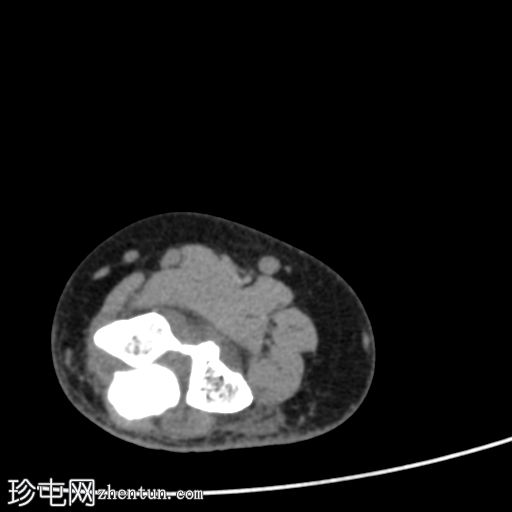

轴向骨窗

显示整个桡骨头粉碎性骨折,特征为两个以上大骨折块,以及倾斜且受压的关节节。

这表明该骨折为不稳定骨折,根据Mason桡骨头骨折分型,为IIIC型。

远端肱骨和可见尺骨未见骨折征象。

此外,由于关节积血导致关节扩张,肘关节脂肪平面弯曲。